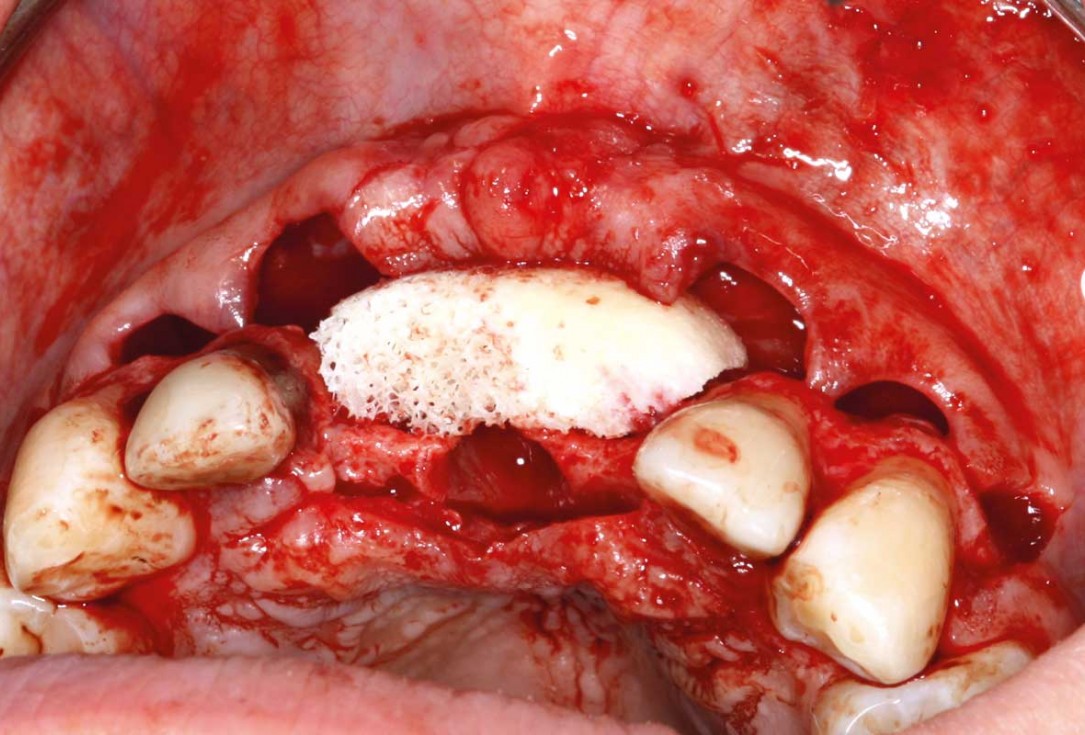

05/26 - Positioning of maxgraft® bonebuilder

Ridge augmentation in the maxilla with maxgraft® bonebuilder in the aesthetic zone - Dr. M. Kristensen